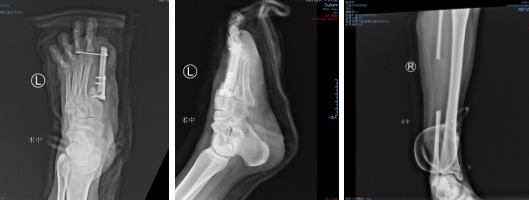

术后DR

术后,就是精心的后续治疗和护理了,让移植的皮瓣与创面慢慢生长“合而为一体”。一周后,观察皮瓣静脉回流正常,顺利成活。两周后,患者皮瓣感觉功能良好。